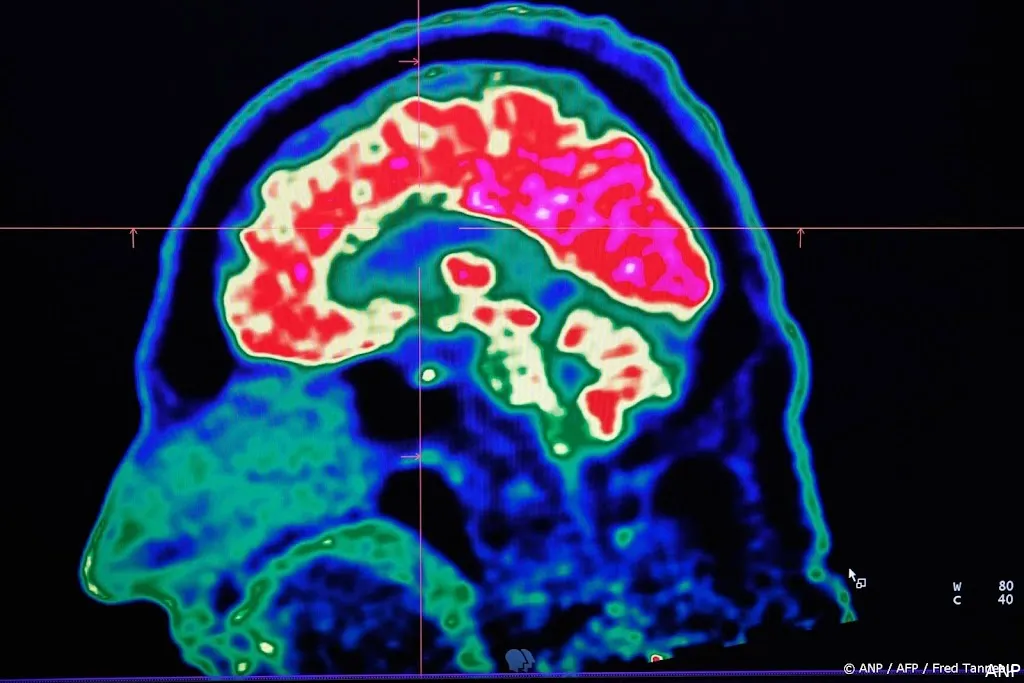

DEN HAAG (ANP) - In de komende decennia moeten steeds meer mensen leven met de gevolgen van een beroerte, dementie of parkinson. Ook hebben veel mensen dan een depressie, een angststoornis of een dwangstoornis. Dat verwacht de Hersenstichting.

De organisatie schat dat halverwege de eeuw meer dan 750.000 mensen een beroerte hebben gehad en met de gevolgen moeten omgaan. Dat zou ongeveer 43 procent meer zijn dan in 2022. De toename komt mede door medische vooruitgang. Mensen overleven vaker een beroerte, maar het betekent wel dat ze lang zorg nodig hebben.

Meer dan een half miljoen mensen hebben rond 2050 dementie, denkt de stichting, wat zou neerkomen op een toename van circa 94 procent.